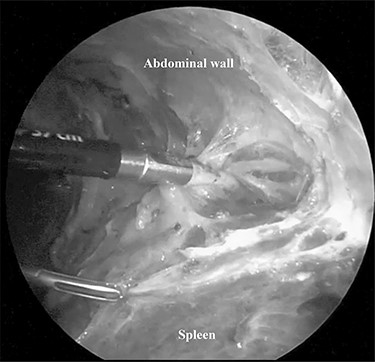

The patient was placed in the right lateral decubitus position. The standing positions of the surgeon and the assistant were on the right or left of the patient depending on the surgical site. Initially, a 12-mm port was introduced through the lateral margin of the left rectus abdominis muscle at the level of the umbilicus. After establishment of pneumoperitoneum with an intra-abdominal pressure of 10 mmHg, two 3-mm ports were inserted in the left upper quadrant at the subxiphoid and left subcostal margin along the mid-axillary line. The accessory spleen was carefully explored through the abdomen. The spleen was mobilized from the lower to upper direction. The initial dissection involved release of the lower pole of the spleen with dissection of the splenocolic ligament, and the spleen was freed from the splenorenal ligament toward the posterior aspect of the splenic hilus using laparoscopic coagulating shears under the guidance of a 3.3-mm needlescope (Karl Storz SE & Co. KG) (Fig. 2). Subsequently, short gastric vessels (Fig. 3) were divided, and the upper pole of the spleen was mobilized with the division of the splenophrenic ligament. Then, the splenic hilus was divided using a linear stapler (Fig. 4). The isolated spleen was then placed in an impermeable bag (Endo-Catch II; Covidien Co. Ltd.) and extracted via a 12-mm port after morcellation using the placenta forceps without extending the initial 12-mm incision (Fig. 5). After irrigation with normal saline and confirmation of hemostasis around the resected area without inserting a suction drain, only the 12-mm port site was only closed, and the 3-mm port sites were left open.

The spleen was freed from the splenorenal ligament using laparoscopic coagulating shears.